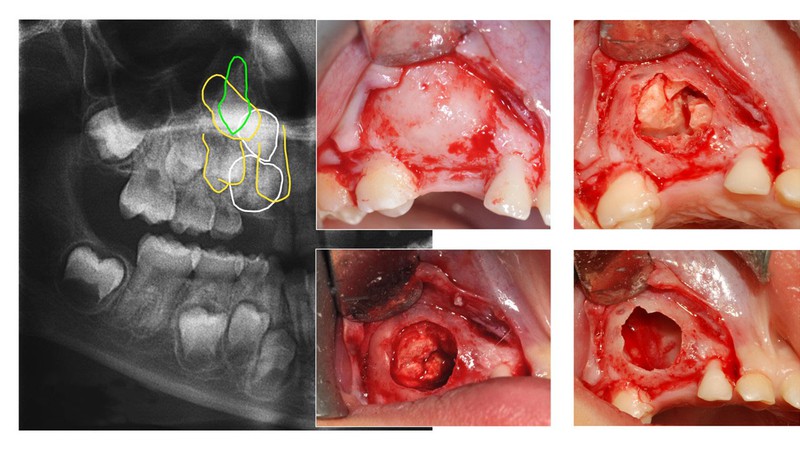

This training session is intended to provide full understanding and techniques for all kinds of teeth extractions. It illustrates how to proceed on all teeth, including premolars and wisdom teeth. The types of flaps and the suture techniques to use will be fully displayed.- Radiographic examinations

- Teeth in the dental arch and impacted teeth

- Bone resection and odontotomy

- Simple and impacted tooth extractions, removal of tooth roots

- Surgical extractions of upper and lower wisdom teeth